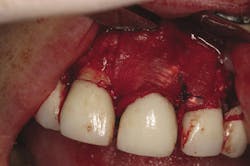

Retention of periodontally compromised teeth with initial, surgical, and supportive therapy has been shown to have high long-term success rates in the literature.3,4 Typical periodontal treatment for patients with moderate to advanced disease when first presenting to a dental office can consist of quadrant scaling and root planing, osseous surgery with or without regenerative therapy (Figs. 1 and 1a), and supportive periodontal maintenance at specific intervals. Estimated totals for this type of "start-up" treatment are in the range of $2,000 to $4,000 depending on geographic location (see Table A). This treatment, if maintained by the patient with diligent home care, has proven to be effective in terms of the prevention of further periodontal progression and tooth retention over a long-term period.5